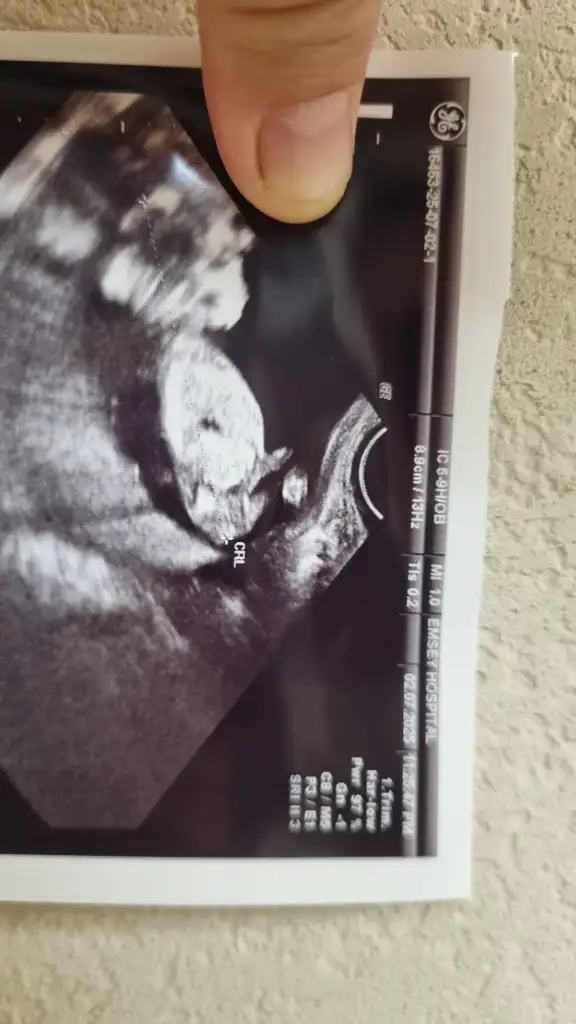

Bacaklarını toplamış gibi burada amasadece tahmin ettim doktorunuz öyle dediyse kızdır![]()

Ultroson fotoğrafından pek belli olmuyor sizin genelde nub teorisi doğru çıkıyor nub gözükmüyor sizinkindeBacaklarını toplamış gibi burada ama

Bacaklarını toplamış o yüzden pek gözükmüyor 10 haftalık bir görüntüsü var vajinal daha net gibi atayım bakınUltroson fotoğrafından pek belli olmuyor sizin genelde nub teorisi doğru çıkıyor nub gözükmüyor sizinkinde

Basi sag tarafta kuyruk sol taraftaSizinkinde başı bile göremedim ben![]()